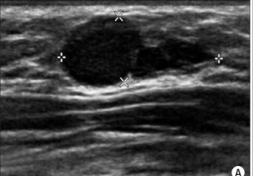

Fibroadenomas

Fibroadenomas usually present as a lump or a change detected on ultrasound/mammogram. Fibroadenomas can vary in size, with some women having more than one. Diagnosis is by core biopsy.

Fibroadenomas are common and thought to be related to estrogen. Although they can appear at any age, they are more likely when aged 15-40 years.

Fibromas are found in the breast lobule and fibrous tissue. Fibroadenomas occurs when tissue in the lobule overgrows and becomes hard.

Most will shrink over time, so are usually left alone. If a fibroadenoma becomes larger or is painful referral to a breast specialist should be made regarding excision.